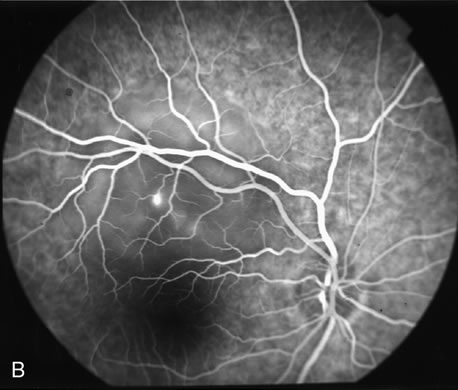

Central serous chorioretinopathy (CSC) is characterized by breakdown of the outer retinal barrier, with leakage of fluid through a defect in the retinal pigment epithelium into the subretinal space, resulting in a serous neurosensory detachment.78–205 The ophthalmologist can usually diagnose CSC based on the clinical examination and demographic information.93–95 Most patients with CSC are middle-aged men74 who often have type A personalities.75, 96–104 CSC has also been associated to the use of corticosteroids,105–118 pregnancy,119–126 increased adrenaline level and stress,127–132 hemodialysis,133,134 collagen vascular diseases,135–147 and hypertension.148–157 CSC typically presents as a large serous detachment in the posterior pole without an obvious source of the subretinal fluid.76 However, because a small CNV cannot be ruled out, FA is usually done to confirm the diagnosis. Characteristically, there is a small RPE defect, which hyperfluoresces early, and then there is slow filling of the overlying neurosensory detachment, which may have a classic “smokestack” (Fig. 21) or “ink blot” (Fig. 22) appearance.158–161 Occasionally, FA demonstrates multiple sites of leakage (Figs. 23, 24, and 25). FA sometimes fails to distinguish CSC from CNV readily because fibrinous subretinal precipitates can cause slow filling of the RPE detachment, which is suggestive of CNV (Fig. 26). Sometimes peripapillary PCV can cause a neurosensory macular detachment masquerading as CSC (Fig. 27).77

Fig. 24. A 34-year-old Caucasian man presented, complaining of blurred vision in his left eye of 1-week duration. A. Clinical photograph of the left eye shows serous neurosensory macular detachment. B and C. Fluorescein angiography demonstrates a pinpoint area of hyperfluorescence in the central macula, leading to the characteristic smokestack configuration seen in the late-phase angiogram. A pigment epithelial detachment temporal to the fovea is increasing in hyperfluorescence throughout the study (white arrows).